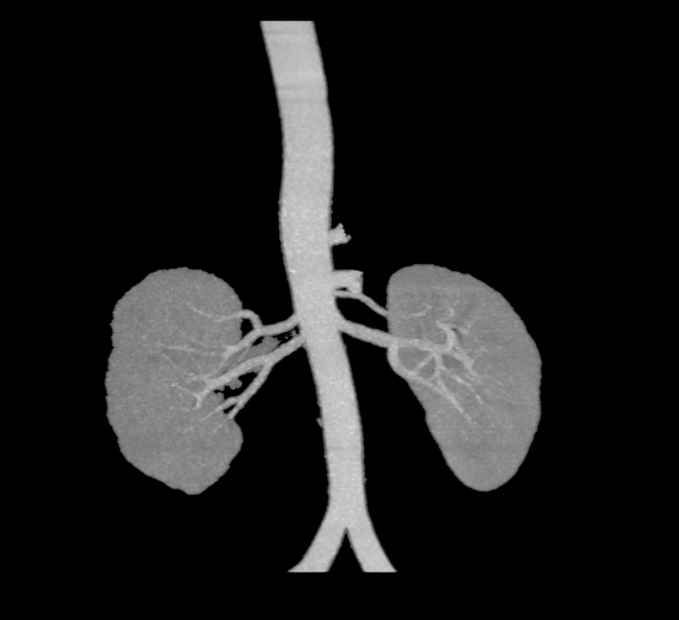

3.基于肾动脉解剖结构的器械选择

解剖特点及器械选择:患者左右肾动脉分支相对迂曲,为了达到更好的降压原则,本着“应消尽消”的原则,选择通过性较好的4F Symplicity Spyral™多级肾动脉射频消融导管,以及6F Launcher RDC导管(55cm).

4.手术策略:左侧消融主干+分支+副肾动脉;右侧消融:主干+分支)

左肾动脉交感神经消融:

主干+分支+副肾动脉

消融点数:35

右肾动脉交感神经消融: